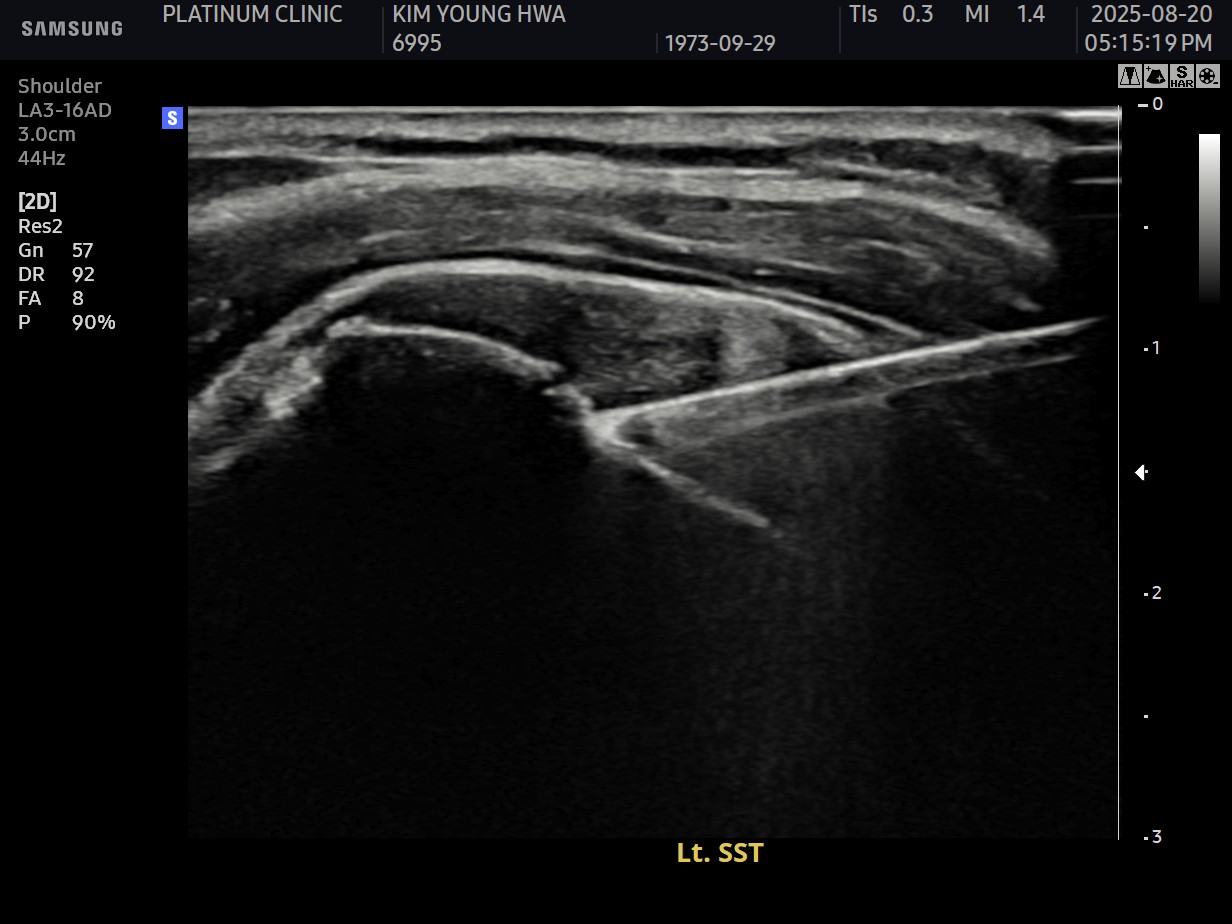

X-ray와 MRI, 초음파 검사를 시행했습니다.

진단 결과:

- ✓석회성건염: 극상건에 약 1.4cm 석회 (휴지기)

- ✓회전근개 관절면측 부분파열: 약 40%

두 가지 문제가 동시에 있었습니다.

시술 과정

시술 시간: 약 50분 (석회 제거 30분 + 봉합술 20분)

10주 후 초음파:

봉합 부위가 정상 인대처럼 하얗게 재생되어 있었습니다. 골수자극의 효과로 예상보다 빠른 재생이 확인되었습니다.